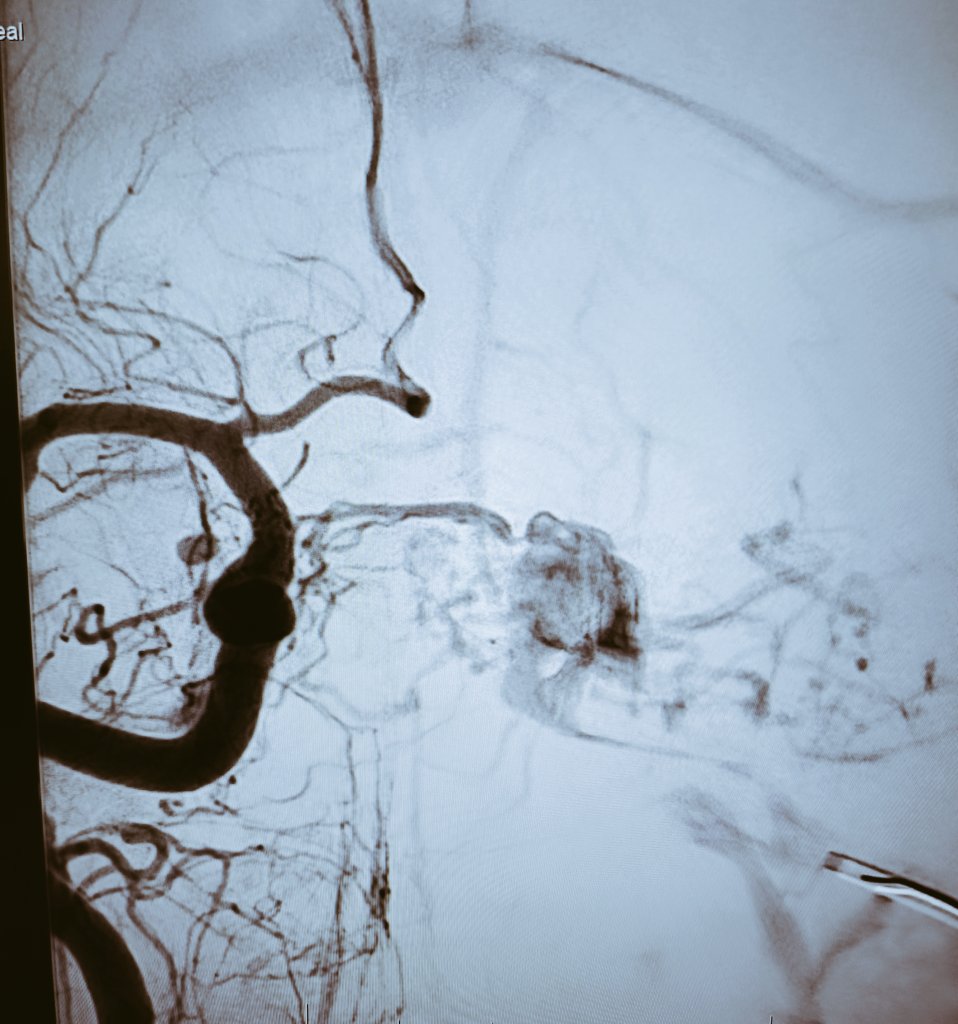

Mycotic (infectious) cerebral aneurysm (CA) resulting from infection of the arterial wall secondary to bacterial endocarditis. Represent < 5% of all CA

We treated it with endovascular glue (NBCA) embolization, complete closure, no deficit